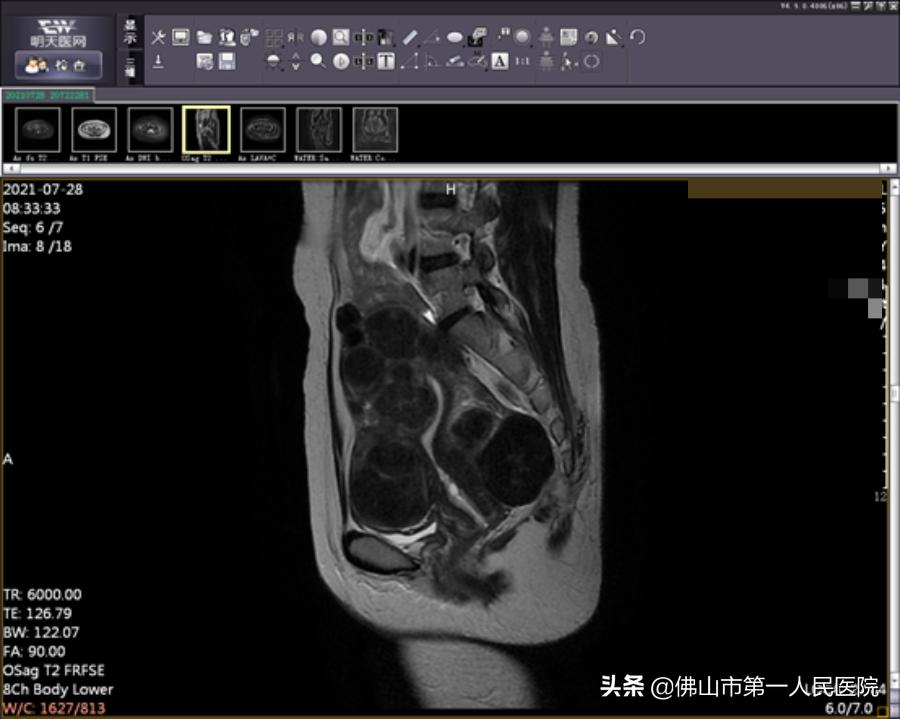

术后图像(海扶使肿瘤组织发生凝固性坏死)

海扶刀手术时长2小时50分钟,治疗时间25分钟。王女士表示术中无明显不适,术后数小时后就能下床正常活动。术后复查磁共振提示消融效果满意,术后月经量正常,术后复查MRI肌瘤消融满意。